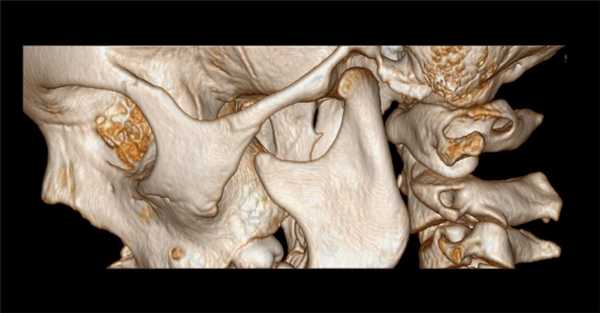

3. КТ при аномалии Киммерле:

• КТ в костном окне:

о Полный или частичный костный мостик над отверстием позвоночной артерии в С1

• КТА:

о Позвоночная артерия в костном туннеле

о Мультипланарная КТ в костном окне с 3D реформатированием